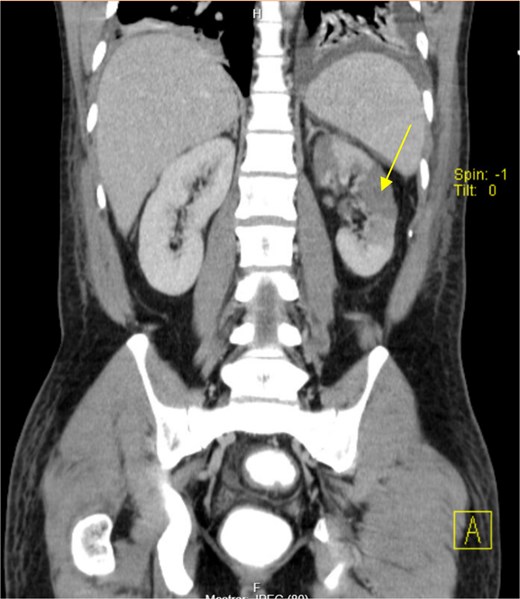

The patient presented at our Emergency Department with a sudden, diffuse, intense abdominal pain. Upon physical examination, the patient’s blood pressure was measured at 132/76 mmHg, heart rate of 103 bpm and a temperature of 39.4°C. The abdominal examination showed a rigid abdomen, with diffuse tenderness, suggesting an acute abdomen scenario. Laboratory tests revealed elevated inflammatory parameters. A abdominal and pelvic computed tomography scan revealed pneumoperitoneum and free fluid in the right iliac fossa and pelvis (Fig. 1). An exploratory laparotomy was proposed and the intraoperative findings included a sigmoid colon perforation with faecal peritonitis. They proceed with sigmoidectomy and temporary abdominal closure, planning for a reintervention to restore gastrointestinal continuity. This was done, after 48 h, through mechanical latero-lateral colo-colic anastomosis. The histopathological examination confirmed diverticulosis with perforation. The patient was subsequently transferred to the intensive care unit, for 5 days. Posteriorly, he developed severe left lumbar pain and hypertension unresponsive to medication. A CT scan revealed left kidney acute ischemia due to left renal artery thrombosis (Fig. 2). Broad-spectrum antibiotic therapy and anticoagulation, was initiated, after assessment by the Vascular Surgery and Urology teams. During his hospitalization, the patient experienced additional thrombotic events, such as occlusion of the left radial artery, and right lower lobar pulmonary embolism. A workup for prothrombotic conditions was conducted, including tests for thrombophilia, lupus, cardiolipins, antinuclear antibody, total protein test, and immunoglobulins, all of which were negative. An angiography of the abdominal aorta revealed arterial microaneurysms in the splanchnic territories: hepatic, perigastric and mesenteric arteries, suggesting polyarteritis nodosa (Fig. 3). Echocardiogram showed no abnormalities. The patient also underwent a study of the left shoulder due to repetitive pain complaints, with a suspected rupture of the rotator cuff. Electromyography excluded peripheral nerve damage. No other complications were reported. The patient was discharged on the 21st day after surgery, under anticoagulation therapy and steroids due to a suspected diagnosis of polyarteritis nodosa. Twenty-seven days after surgical intervention, the patient returned to the ED, presenting with abdominal pain in the lower quadrants and nausea. He was hemodynamically stable with abdominal pain and tenderness on the left flank and iliac fossa. Laboratory tests revealed leukocytosis and hyperlactacidemia. The CT scan reported free fluid, free gas bubbles adjacent to the sigmoid which had a concentric circular thickening of the wall, just distal to the previous anastomosis (Fig. 4). An exploratory laparotomy was performed, during which a large hematoma on the wall of the left colon was identified, with no apparent signs of perforation. A peritoneal lavage, drainage, and a derivative ileostomy were carried out. During the post-operative period the patient maintained a small volume of purulent discharge through the abdominal drain, with no abdominal tenderness. A reevaluation CT scan was performed, highlighting a regression of the hematoma of the colonic wall but raised suspicion of a low output fistula near the anastomosis. Since the patient maintained hemodynamic and analytical stability, he was discharged from the hospital with home care, including an abdominal drain, parenteral nutrition, empirical antibiotic therapy, and gradual reduction in the steroid dosage. The patient was referred to the ED, on Day 6, due to enteric drainage. An enterocutaneous fistula was diagnosed, and he was readmitted. He received 12 days of full-dose parenteral nutrition, which reduced the fistula output and improved his clinical and analytical status. Due to residual drainage volume and an analytical and imagiologic improvement, the drain was removed, and the patient was discharged, tolerating an oral diet, and with a functioning ileostomy.

(a) Pneumoperitoneum (arrowheads). (b) Free fluid in the right iliac fossa (arrowhead). (c) Free fluid in the pelvis (arrowhead).